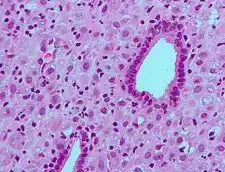

Micrograph showing changes to the endometrium due to progesterone (decidualization) H&E stain.